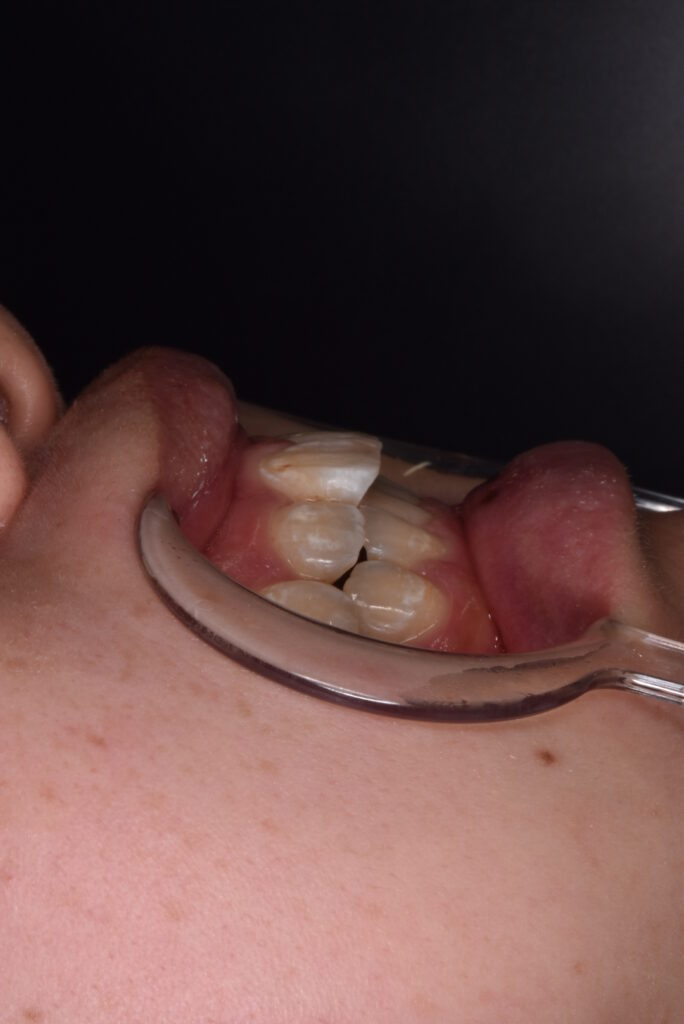

矯正前

前歯の突出感と下の歯の叢生が目立ちます。